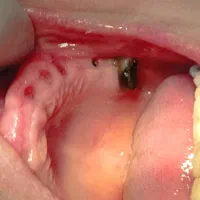

خدمات دندانپزشکی تخصصی توسط دندانپزشک و جراح دهان و فک و زیبایی و ایمپلنت های دندانی و رتبه برتر دانشگاه با دستگاه بیحسی بدون درد دیجیتالی جراح و دندانپزشک دقیق و با حوصله و با وجدان کاری و درمان های تضمینی خدمات دندانپزشکی از لحاظ کیفیت یکی نیست و خدمات بی کیفیت باعث از بین رفتن دندان و ترس از دندانپزشکی میشود کاشت انواع ایمپلنت های کره و سوییس و آلمان با اسکنر ۳بعدی و کمترین قیمت که ایمپلنت های آلمانی گارانتی مادام العمر داره و بلافاصله امکان قالبگیری و گذاشتن روکش هست با اقساط منعطف و بلند مدت و شرایط و قیمت های عالی نسبت به کیفیت خدمات درمانی نسل جدید ایمپلنت های دیجیتال و بازسازی استخوان برای کاشت ایمپلنت در فک تحلیل رفته با بیحسی عمیق یا بیهوشی و اوردنچر های ثابت با طراحی پیشرفته و ظریف متکی بر ایمپلنت یا دندان های طبیعی محیط شیک و کاملا بهداشتی و مجهز به تجهیزات به روز درمان ریشه تخصصی و درمان مجدد خدمات معیوب و غیر اصولی دیگر در گذشته زیبایی خط لبخند با روکش،لمینیت و کامپوزیت نسل ۸ توسط جراح دهان و درمان ریشه و زیبایی نمونه کار در پیج اینستا جهت نوبت دهی،مشخصات و شماره بزارین